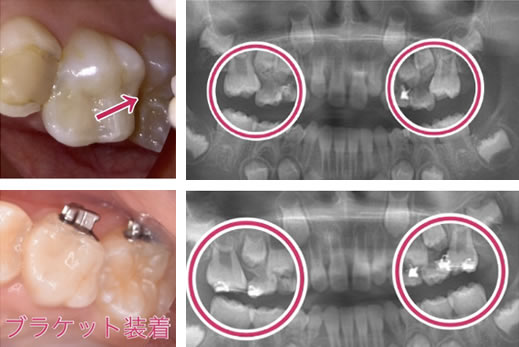

ブラケットを装着して、6歳臼歯を後ろに移動させ、萌出させる事です。状態によっては、他の方法もあります。

手間の乳臼歯は、根が溶けて吸収しているので、早く抜けてしまう事が多いです。そのような場合、せっかく良い位置に移動させた6歳臼歯が、再び手間に倒れてきてしまうので、保隙装置を装着する必要があります。

6歳臼歯の放出遅延をそのままにするとさらに前に傾いて

噛み合わせが悪くなります。

また、虫歯になってしまう事があります。

引っかかる原因の乳臼歯を抜くと、6歳臼歯は前に寄りながら萌出してしまうので、

抜いた乳臼歯の下にある永久歯が萌出するスペースが無くなってしまいます。